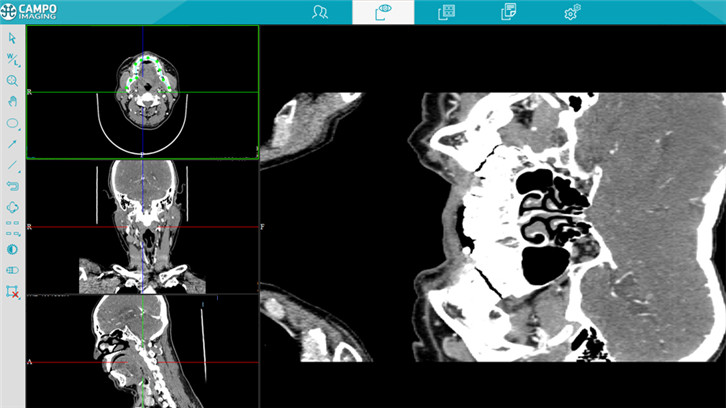

图像浏览

多平面重建

虚拟内窥镜